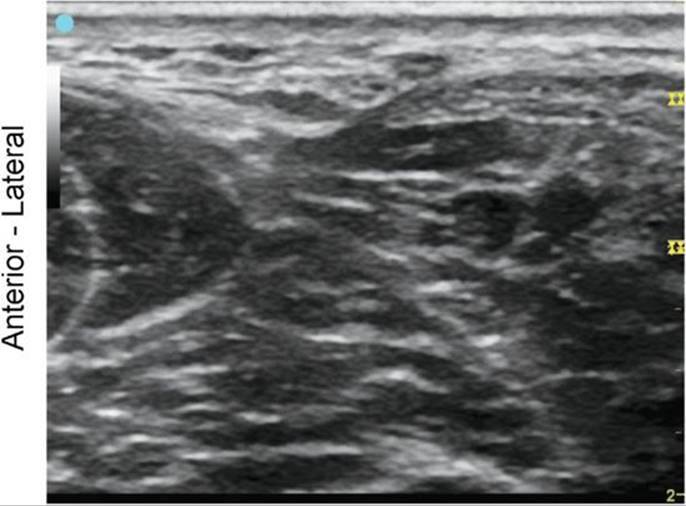

Peroneal Nerve, Deep and Superficial Branches at the Level of the Ankle

FIGURE 7.58.1A Ultrasound transducer position to image the peroneal nerve, deep and superficial branches at the level of the ankle.

FIGURE 7.58.1B Ultrasound image of the peroneal nerve, deep and superficial branches at the level of the ankle.

FIGURE 7.58.1C Labeled ultrasound image of the peroneal nerve, deep and superficial branches at the level of the ankle.

FIGURE 7.58.1D Labeled cross-sectional anatomy of the peroneal nerve, deep and superficial branches at the level of the ankle.

Abbreviations: PBM, Peroneus Brevis Muscle; EDL, Extensor Digitorum Longus; SPN, Superficial Peroneal Nerve; DPN, Deep Peroneal Nerve; ATA, Anterior Tibial Artery.